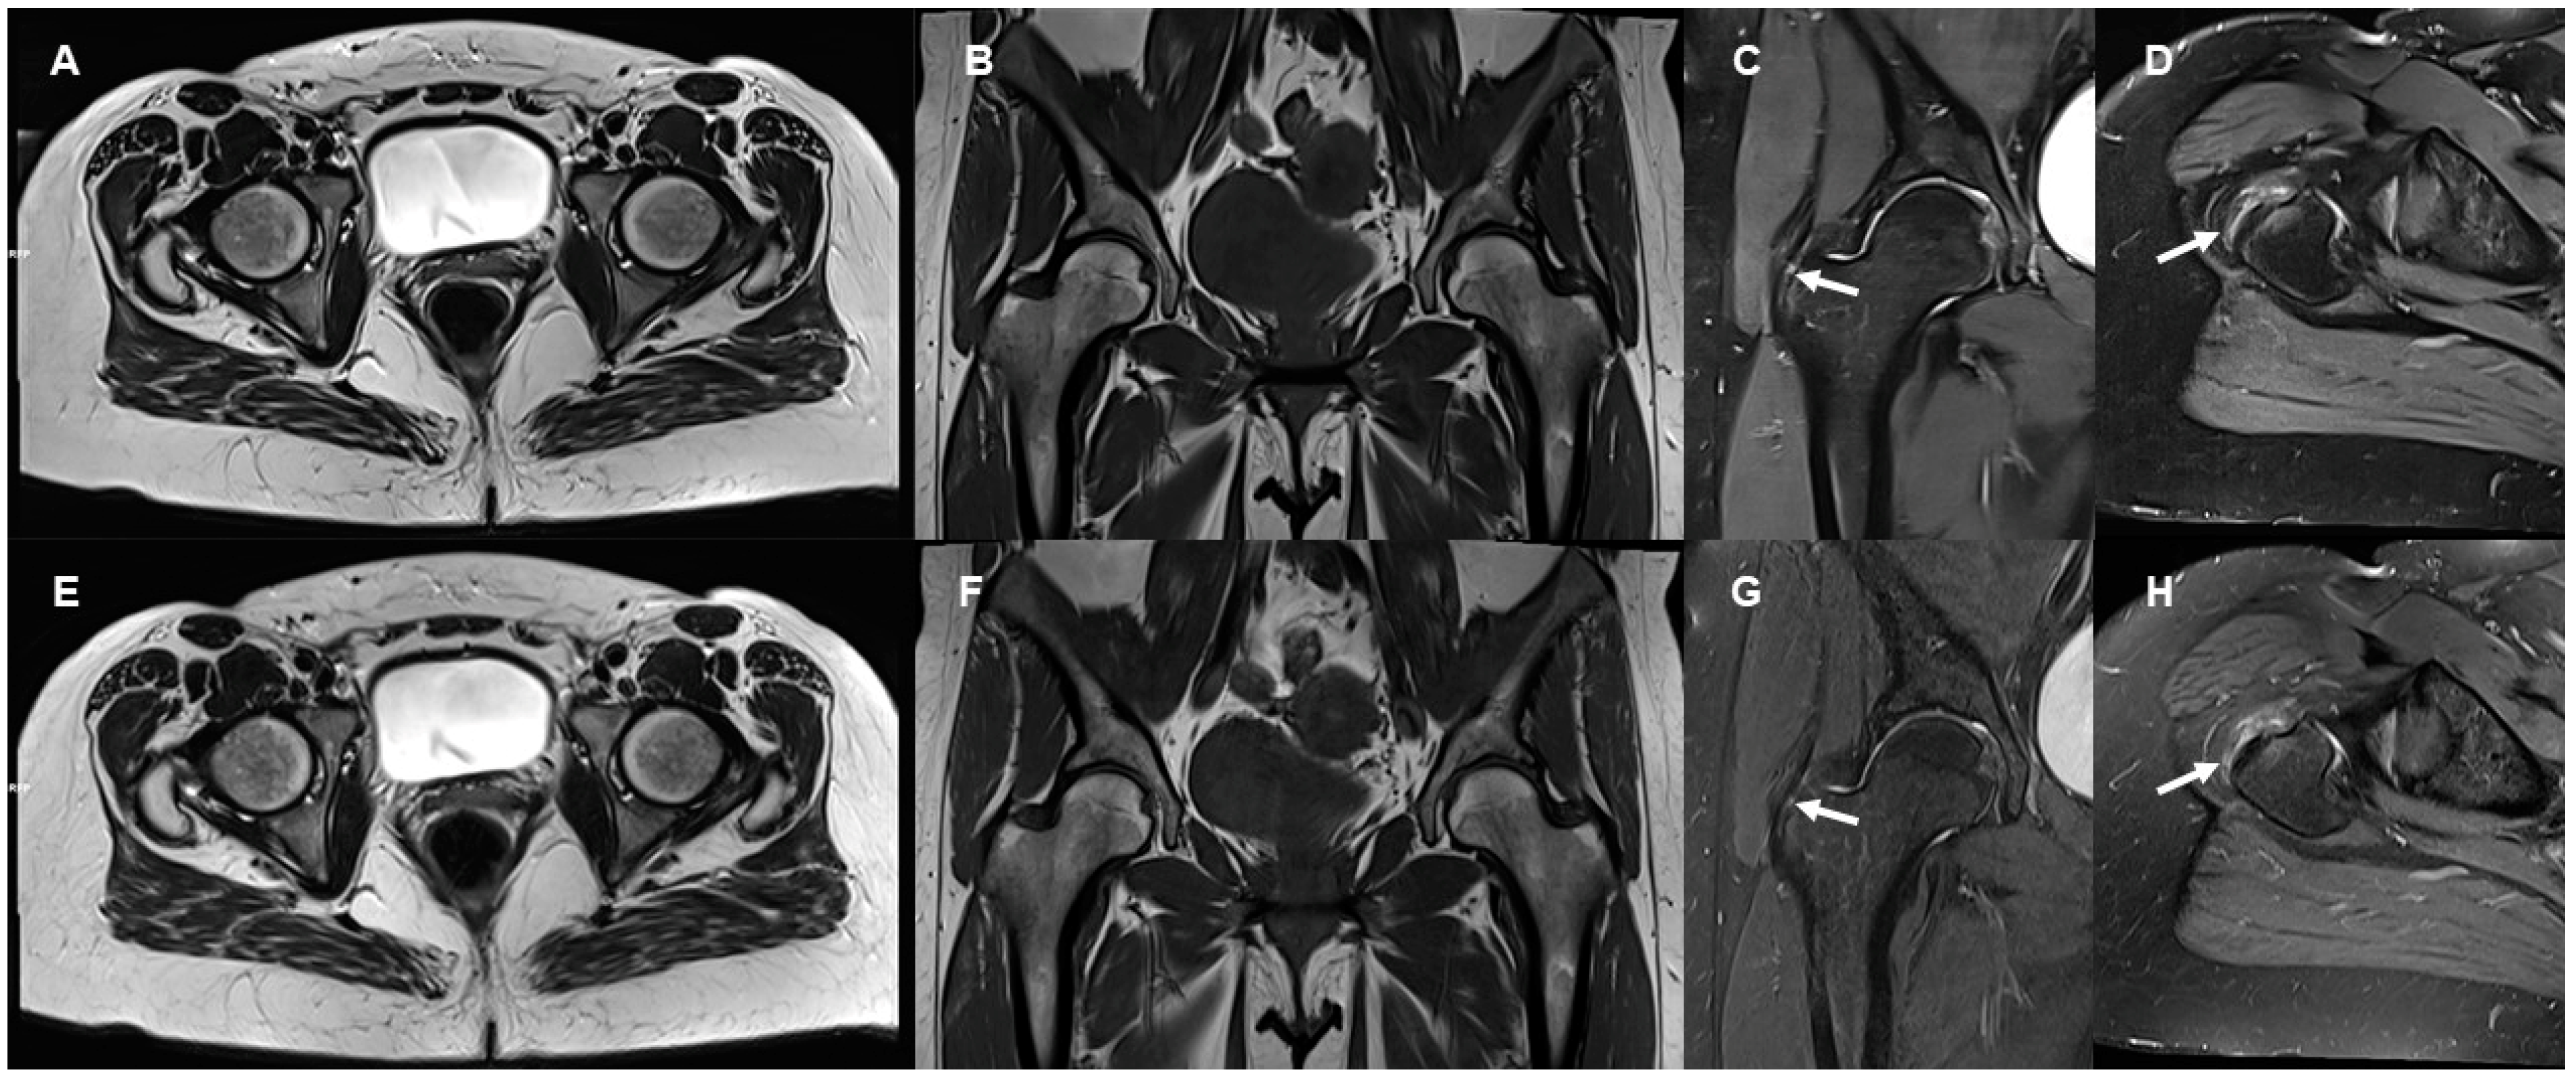

3.2. Delineation of Anatomic Structures and Internal Derangement